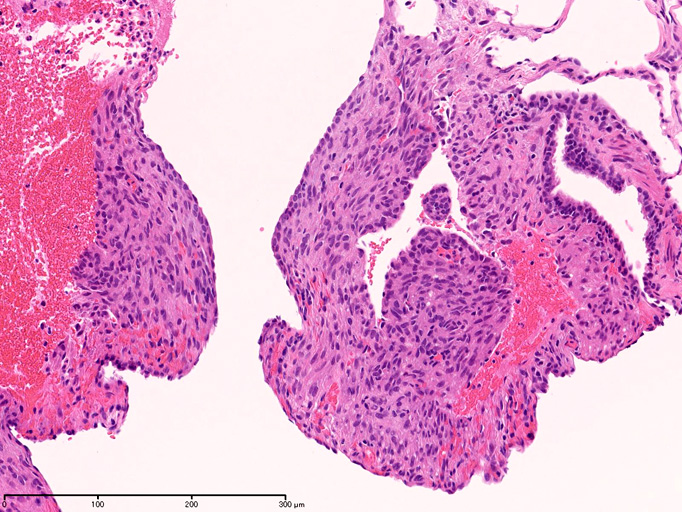

LAMの肺病変

嚢胞周囲または肺血管, リンパ管, 細気管支にそうLAM cellの浸潤, 集簇を特徴とする。LAM cellには2種類が認められ, 小型紡錘形細胞と細胞質の豊富な類上皮様細胞があり, 紡錘型は主に集簇巣の中心に存在し増殖能が高い。 類上皮様LAM cellは辺縁部に多く, 増殖能は低いがHMB45を強く発現している。

LAM cellの免疫染色--SMA, desmin, vimentin(vimentinはいつも陽性とはならない)が陽性となりmuscle lineageであるが典型的な筋細胞と異なり,